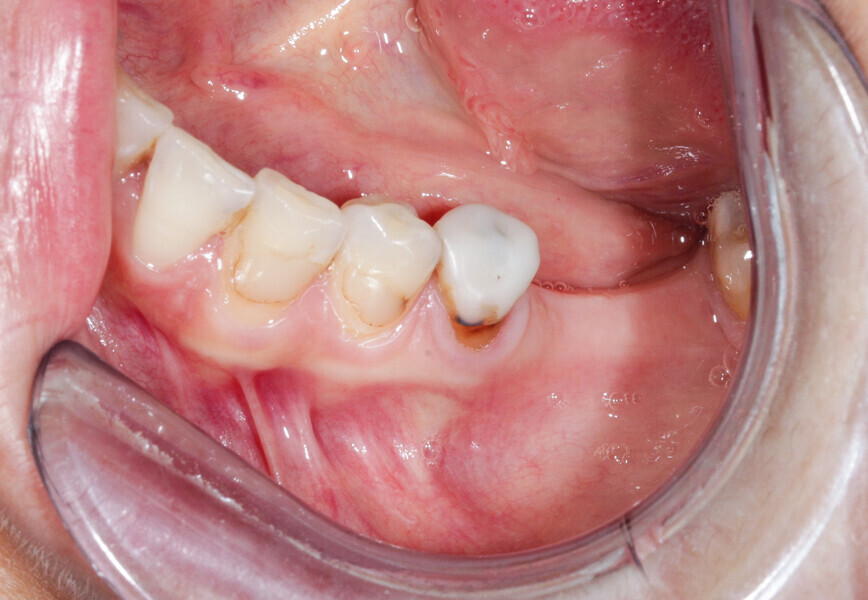

A 36-year-old patient with teeth #36 and 37 missing and transverse bone insufficiency in the existing gap was treated. It would have been possible to place implants, but this would have left only a thin layer of vestibular bone at the neck of the implants. There was a serious risk of dehiscence, which can compromise the survival of the implant in the arch (Fig. 4).

We had three alternative courses of action: a bone block graft from the mandibular ramus,2 a segmental osteotomy4 or a radicular graft, knowing that tooth #46 could not be saved. We chose the third option because it allowed for simultaneous implant placement and bone reconstruction. A large flap was elevated to assess the gap in the bone and in anticipation of closing the flap on an augmented ridge. Two implants were placed as normal despite the low residual bone thickness in the vestibular area of the planned positions for the implants (Fig. 5). The roots of tooth #46 were extracted atraumatically (root separation, use of piezo-surgery, etc.) and were then prepared as described. The roots were shaped to fit the defect and fixated at the insertion site using osteosynthesis screws (Fig. 6).3 The flap was mobilised and stretched to achieve edge-to-edge closure without tension, and a 4/0 rapidly resorbed braided thread was used for the sutures (Fig. 7). Four months after the bone augmentation and implant placement, healing abutments were connected to the implants and the osteosynthesis screws removed (Figs. 8 & 9). During the operation, time was taken to perform a visual check that ankylosis of the radicular grafts had been successful and that these were sound. Finally, a CBCT assessment was performed. The prosthesis was fitted by our colleague a few weeks later, once the soft tissue had healed.